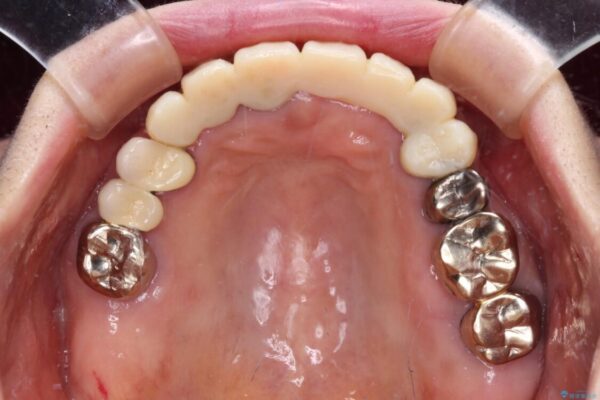

抜歯の必要な前歯や、以前治療した前歯のクラウンの外観を気にして来院された患者様です。

治療前

• 前歯をきれいにしたい インプラントや部分矯正を用いた総合歯科治療 治療前画像